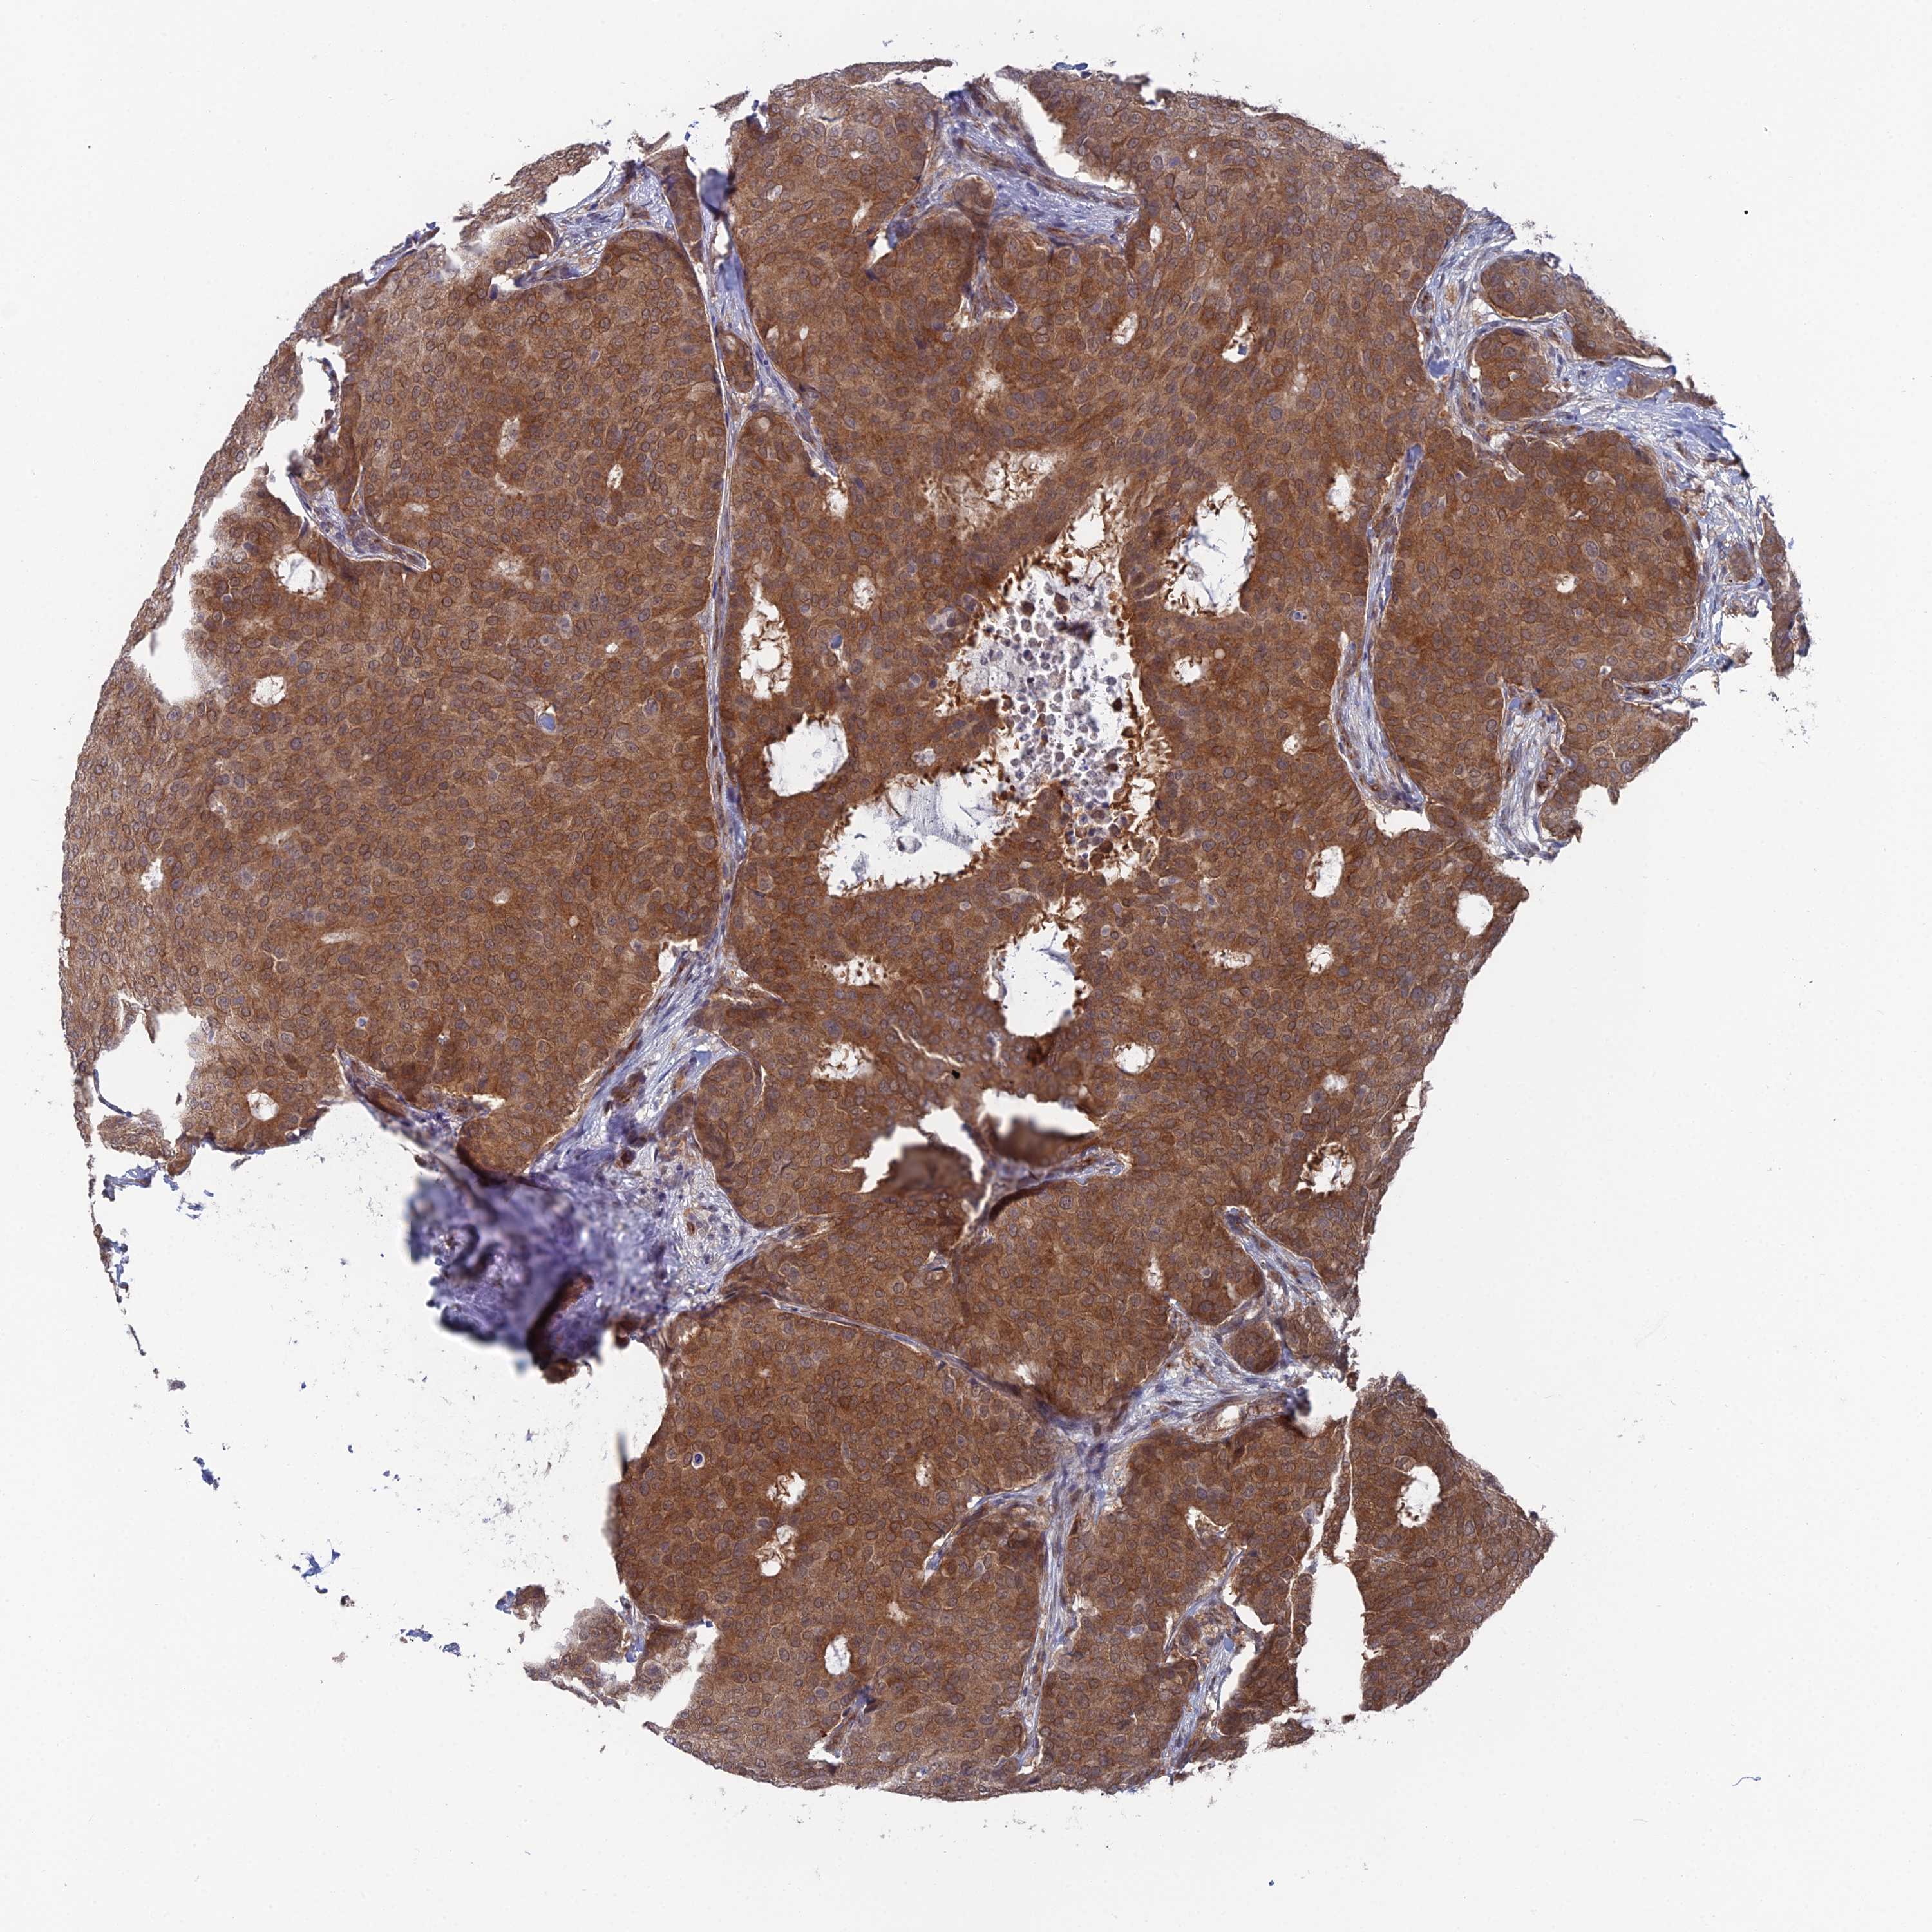

BRCA TCGA BRCA VALIDATION PROTEIN EXPRESSION

ANTIBODIES

AND

VALIDATION